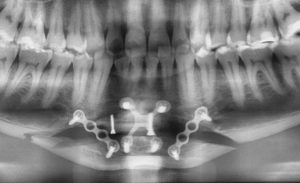

- 3D CT imaging is most informative x ray, lateral cephalometric and panorex at a minimum

- Rigid fixation is mandatory

- Prefer new titanium plates

- Avoid reusing old screw holes when possible

- Consider dual-plate fixation for:

- Vertical lengthening

- Nonunion

- Large advancements

- Allogeneic (tissue bank) corticocancellous chips, used in almost all osteotomy cases

- Pack graft tightly into all gaps after plate fixation applied